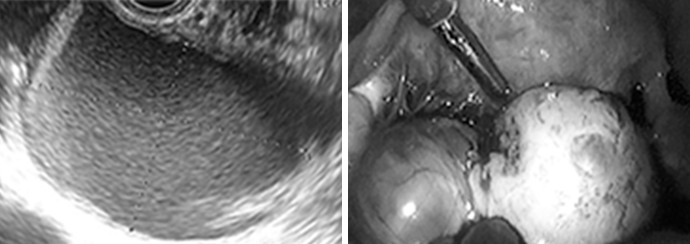

다낭성 난소 증후군

다낭성 난소 증후군은 가임연령 여성의 4-10% 정도까지 보고되고 있으며, 배란장애에 의한 난임의 가장 흔한 원인입니다. 임상증상으로 만성적 무배란 및 이로 인한 무월경/희발 월경, 부정 자궁출혈, 난임 등의 증상과 다모증, 여드름 등이 있을 수 있고, 비만이 많이 동반됩니다. 초음파상 작은 다낭성의 난포들이 관찰되며, 장기적으로는 당뇨, 고콜레스테롤혈증과 같은 대사성 질환과도 관련될 수 있습니다.

자궁경 검사

자궁경 검사는 3-5mm 두께의 자궁경을 질 및 자궁경부를 통해 자궁강 내로 삽입한 후 모니터를 통해 자궁내부의 전, 후벽, 자궁저부, 양측 난관 진입부위 같은 자궁내부를 직접 확인함으로써 자궁강 내의 이상 여부를 확인하고 필요 시 조직검사나 병변이 있을 때에는 특수하게 고안된 기구를 이용하여 시행합니다.